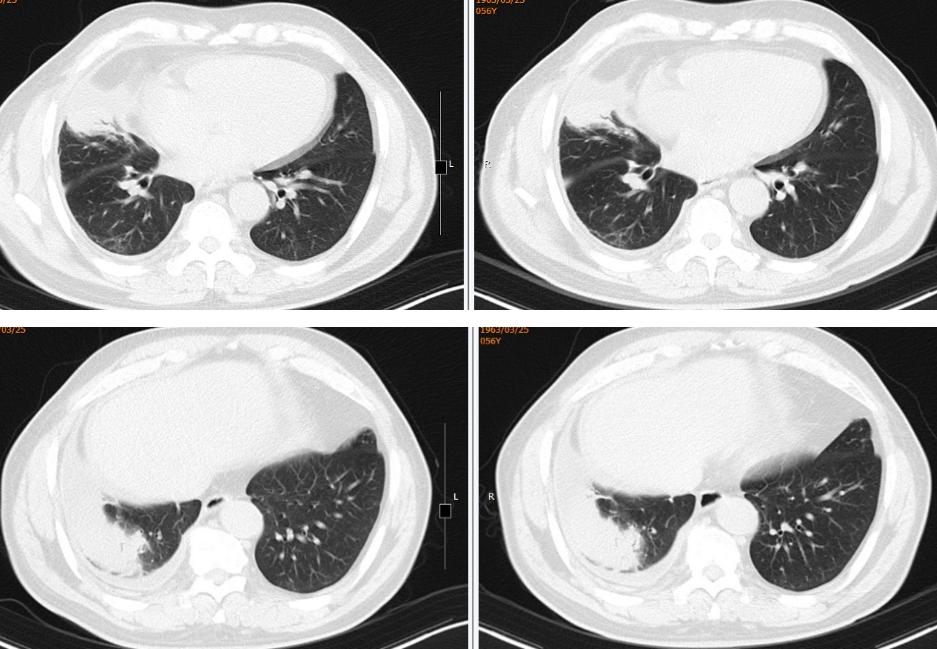

12、胸部CT:右肺中下叶团块、索条灶,右侧胸腔积液(图2)。

图2:胸部CT(2019年08月12日)

1、胸部动脉成像(CTA)(2019-08-14):右肺中下叶团块、条索灶,右侧胸腔积液,较2019-8-12老片积液增多,CTA未见明显充盈缺损(图3)。

(左 2019-08-12;右 2019-08-14)

图3:胸部动脉成像(CTA)(2019-08-14)

(从左至右)初诊、1月后、4月后:

图14:2019-09-16胸部CT(1月后):右肺中下叶团块、索条灶,右侧胸腔积液,较2019-08-14老片病灶略吸收,积液减少。2019-12-16胸部CT(4月后):右肺中下叶团块、索条灶,右侧胸腔积液,较2019-09-16老片病灶略吸收,积液减少。